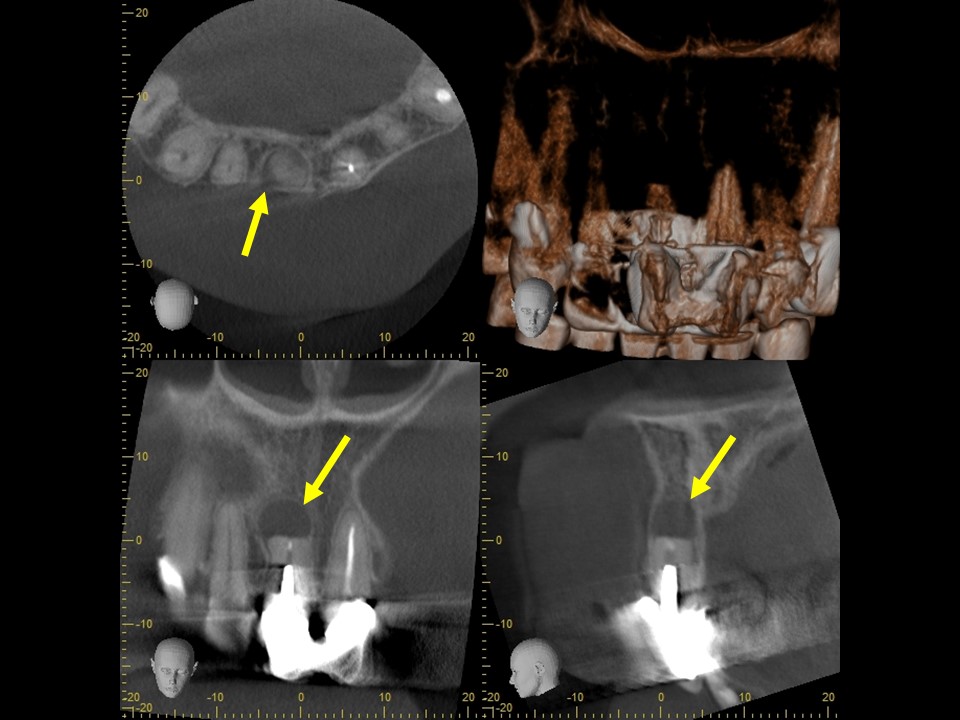

歯根端切除・逆根管充填6か月後レントゲンおよびCT画像です。

根尖部の黒いX線透過像は完全に消失しており、歯槽骨が再生し根尖病変の治癒を認めます。